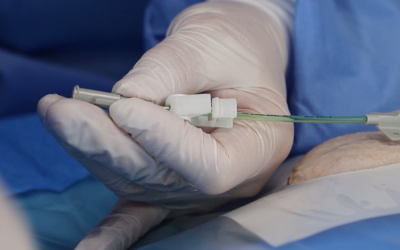

- Técnica de inserción: Seldinger directa o mediante dispositivo integrado todo en uno

- Técnica de inserción: Seldinger modificada/directa